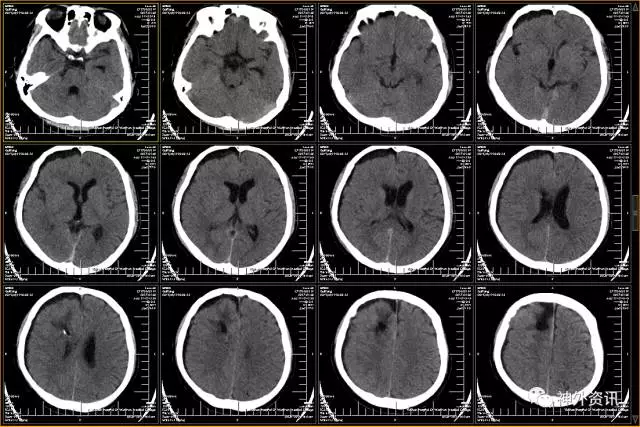

头颅CT示:蛛网膜下腔出血,脑干旁30mm*16mm占位,怀疑颅内动脉瘤可能。

(头颅CT示:蛛网膜下腔出血,左侧颞叶血肿)

(术后头颅CT)

(术后10日头颅CT)

(术后头颅CT)